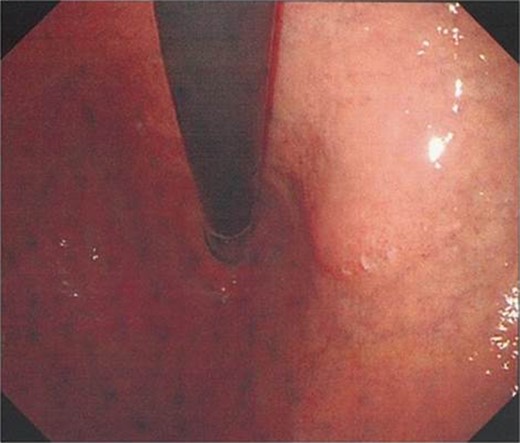

A 72-year-old Japanese woman visited our hospital for a routine health examination and underwent abdominal ultrasonography, which revealed an intra-abdominal tumor. The patient had no symptoms, and the findings of physical and laboratory tests, including carcinoembryonic antigen and carbohydrate antigen 19-9 were unremarkable. The patient had no history of previous illness and was not taking any regular medications. Contrast-enhanced computed tomography (CT) (Fig. 1a) and magnetic resonance imaging (MRI) (Fig. 1b) showed a well-defined, mildly heterogeneous solid mass of about 3 cm in diameter lying adjacent to the stomach. Endoscopy showed the lesser curvature of the stomach to be compressed extraluminally and without mucosal abnormalities (Fig. 2). An endoscopic ultrasonogram revealed a 30 × 25-mm2 low-echoic lesion that was adhered to the side of the lesser curvature of the stomach. Based on these findings, the mass was preoperatively diagnosed as a GIST of the stomach.

Upper endoscopy findings. Upper endoscopy showed the lessor curvature of the stomach to be compressed extraluminally without mucosal abnormalities.